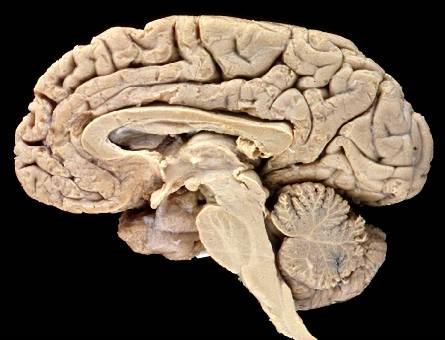

The cerebrum is the largest part of the brain and is responsible for higher brain functions such as thought, memory, and voluntary movement. It is divided into two hemispheres (right and left), each covered by the cerebral cortex, a layer of gray matter. The surface of the cerebrum is marked by gyri (elevated ridges), sulci (shallow depressions), and fissures (deeper grooves), all of which increase the surface area for neural processing.

The brain is organized into four main regions, each with specialized functions:

Cerebrum: Responsible for conscious thought, memory, and voluntary muscle contractions.

Cerebellum: Coordinates complex somatic motor patterns and maintains posture and balance.

Diencephalon: Contains the thalamus (relay and processing center for sensory information) and hypothalamus (centers for emotions, autonomic functions, and hormone production).

Brainstem: Includes the midbrain (processes visual/auditory data, maintains consciousness), pons (relays sensory information, controls respiration), and medulla oblongata (relays sensory information, regulates autonomic functions).